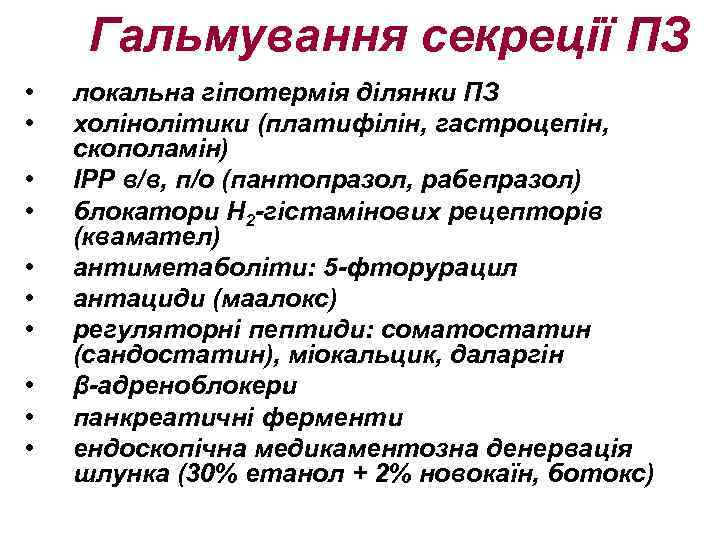

Гальмування секреції ПЗ • • • локальна гіпотермія ділянки ПЗ холінолітики (платифілін, гастроцепін, скополамін) ІРР в/в, п/о (пантопразол, рабепразол) блокатори Н 2 -гістамінових рецепторів (квамател) антиметаболіти: 5 -фторурацил антациди (маалокс) регуляторні пептиди: соматостатин (сандостатин), міокальцик, даларгін β-адреноблокери панкреатичні ферменти ендоскопічна медикаментозна денервація шлунка (30% етанол + 2% новокаїн, ботокс)

Гальмування секреції ПЗ • • • локальна гіпотермія ділянки ПЗ холінолітики (платифілін, гастроцепін, скополамін) ІРР в/в, п/о (пантопразол, рабепразол) блокатори Н 2 -гістамінових рецепторів (квамател) антиметаболіти: 5 -фторурацил антациди (маалокс) регуляторні пептиди: соматостатин (сандостатин), міокальцик, даларгін β-адреноблокери панкреатичні ферменти ендоскопічна медикаментозна денервація шлунка (30% етанол + 2% новокаїн, ботокс)